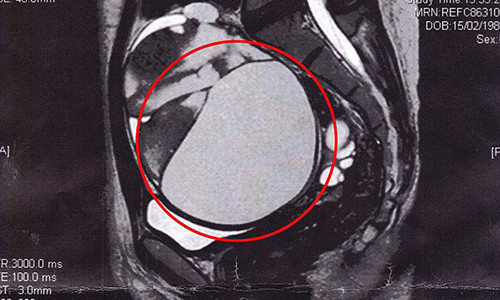

| Khối u với kích thước 16cm ở buồng trứng và nó đang chèn ép các cơ quan nội tạng. |

Sau khi siêu âm, bác sĩ xác định cô có một khối u ung thư với kích thước 16cm ở buồng trứng và nó đang chèn ép các cơ quan nội tạng. Khối u Carcinoid rất hiếm gặp, khối u này làm chậm quá trình phát triển của hệ thống thần kinh nội tiết – hệ thống sản xuất hormone.